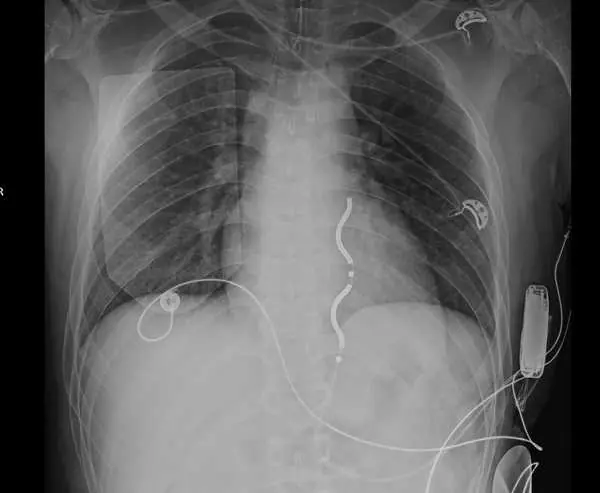

心臟外科魏晧智主任說明,最新的血管外心臟去顫器(簡稱EV-ICD),免除導線經由靜脈進入心臟的路徑,改由特殊的波浪型導線植入在胸骨下方,去顫器則植入在腋下皮下,減少傳統手術可能造成的創傷,更有效降低併發症發生。

圖一:臺中榮總完成台灣首例血管外心臟去顫器植入手術。

圖二:最新的血管外心臟去顫器,免除導線經由靜脈進入心臟的路徑,改由植入特殊的波浪型導線,去顫器則植入在腋下皮下,減少手術創傷及降低併發症。